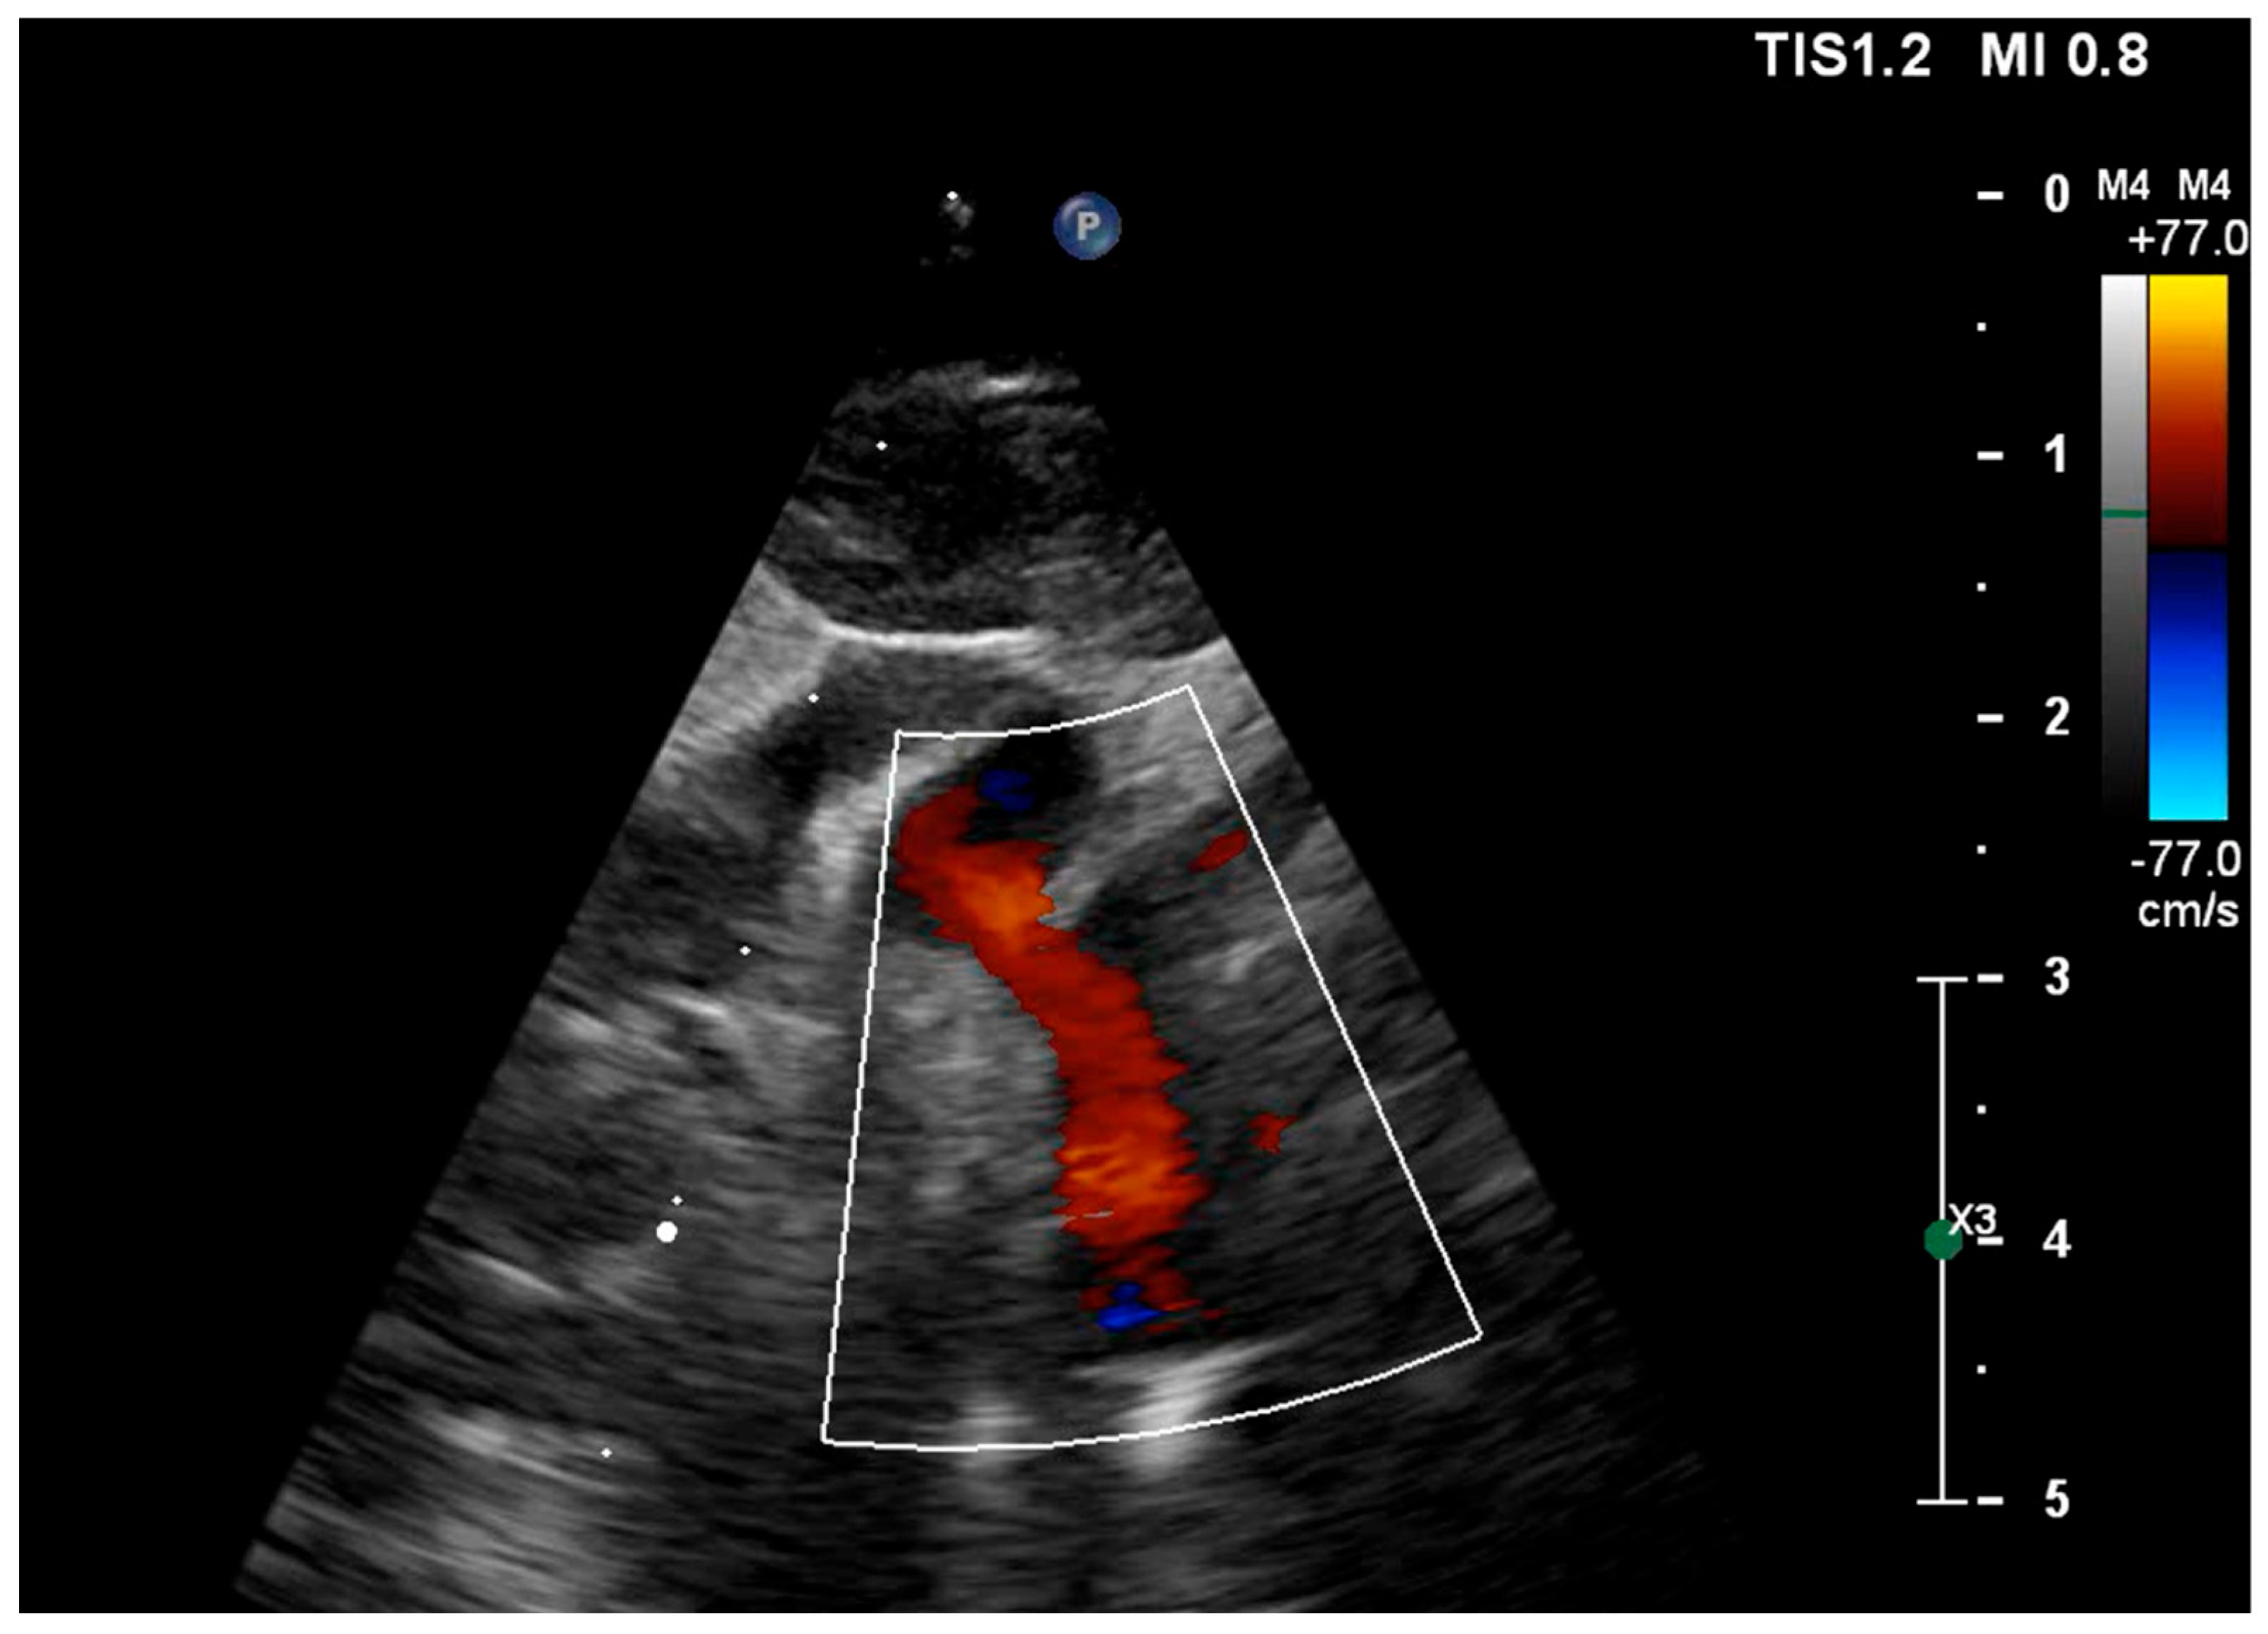

| Ventricular disproportion (TV/MV ratio) | ≥1.5 (Yes) | ≥1.5 (Yes) | ≥1.5 (Yes) | TV/MV ≥ 1.5 indicates significant ventricular disproportion |

| Biphasic transmitral inflow | Present | Present | Present | Biphasic pattern consistent with impaired LV relaxation |

| Restrictive atrial septal defect | No | No | No | Restriction suggested by high-velocity atrial shunt and LA hypertension |